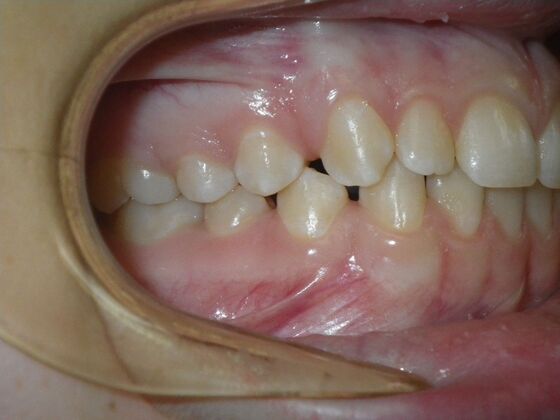

Patient presents desiring all spaces on upper and lower teeth closed. She will need slight expansion of upper arch due to lower molars leaning inward toward tongue. Used nitanium palatal expander with built in rotation of upper molars and lower lip bumper to upright lower first molars. Patient was also informed that her upper lateral incisors would require bonding due to their small size to close all space.